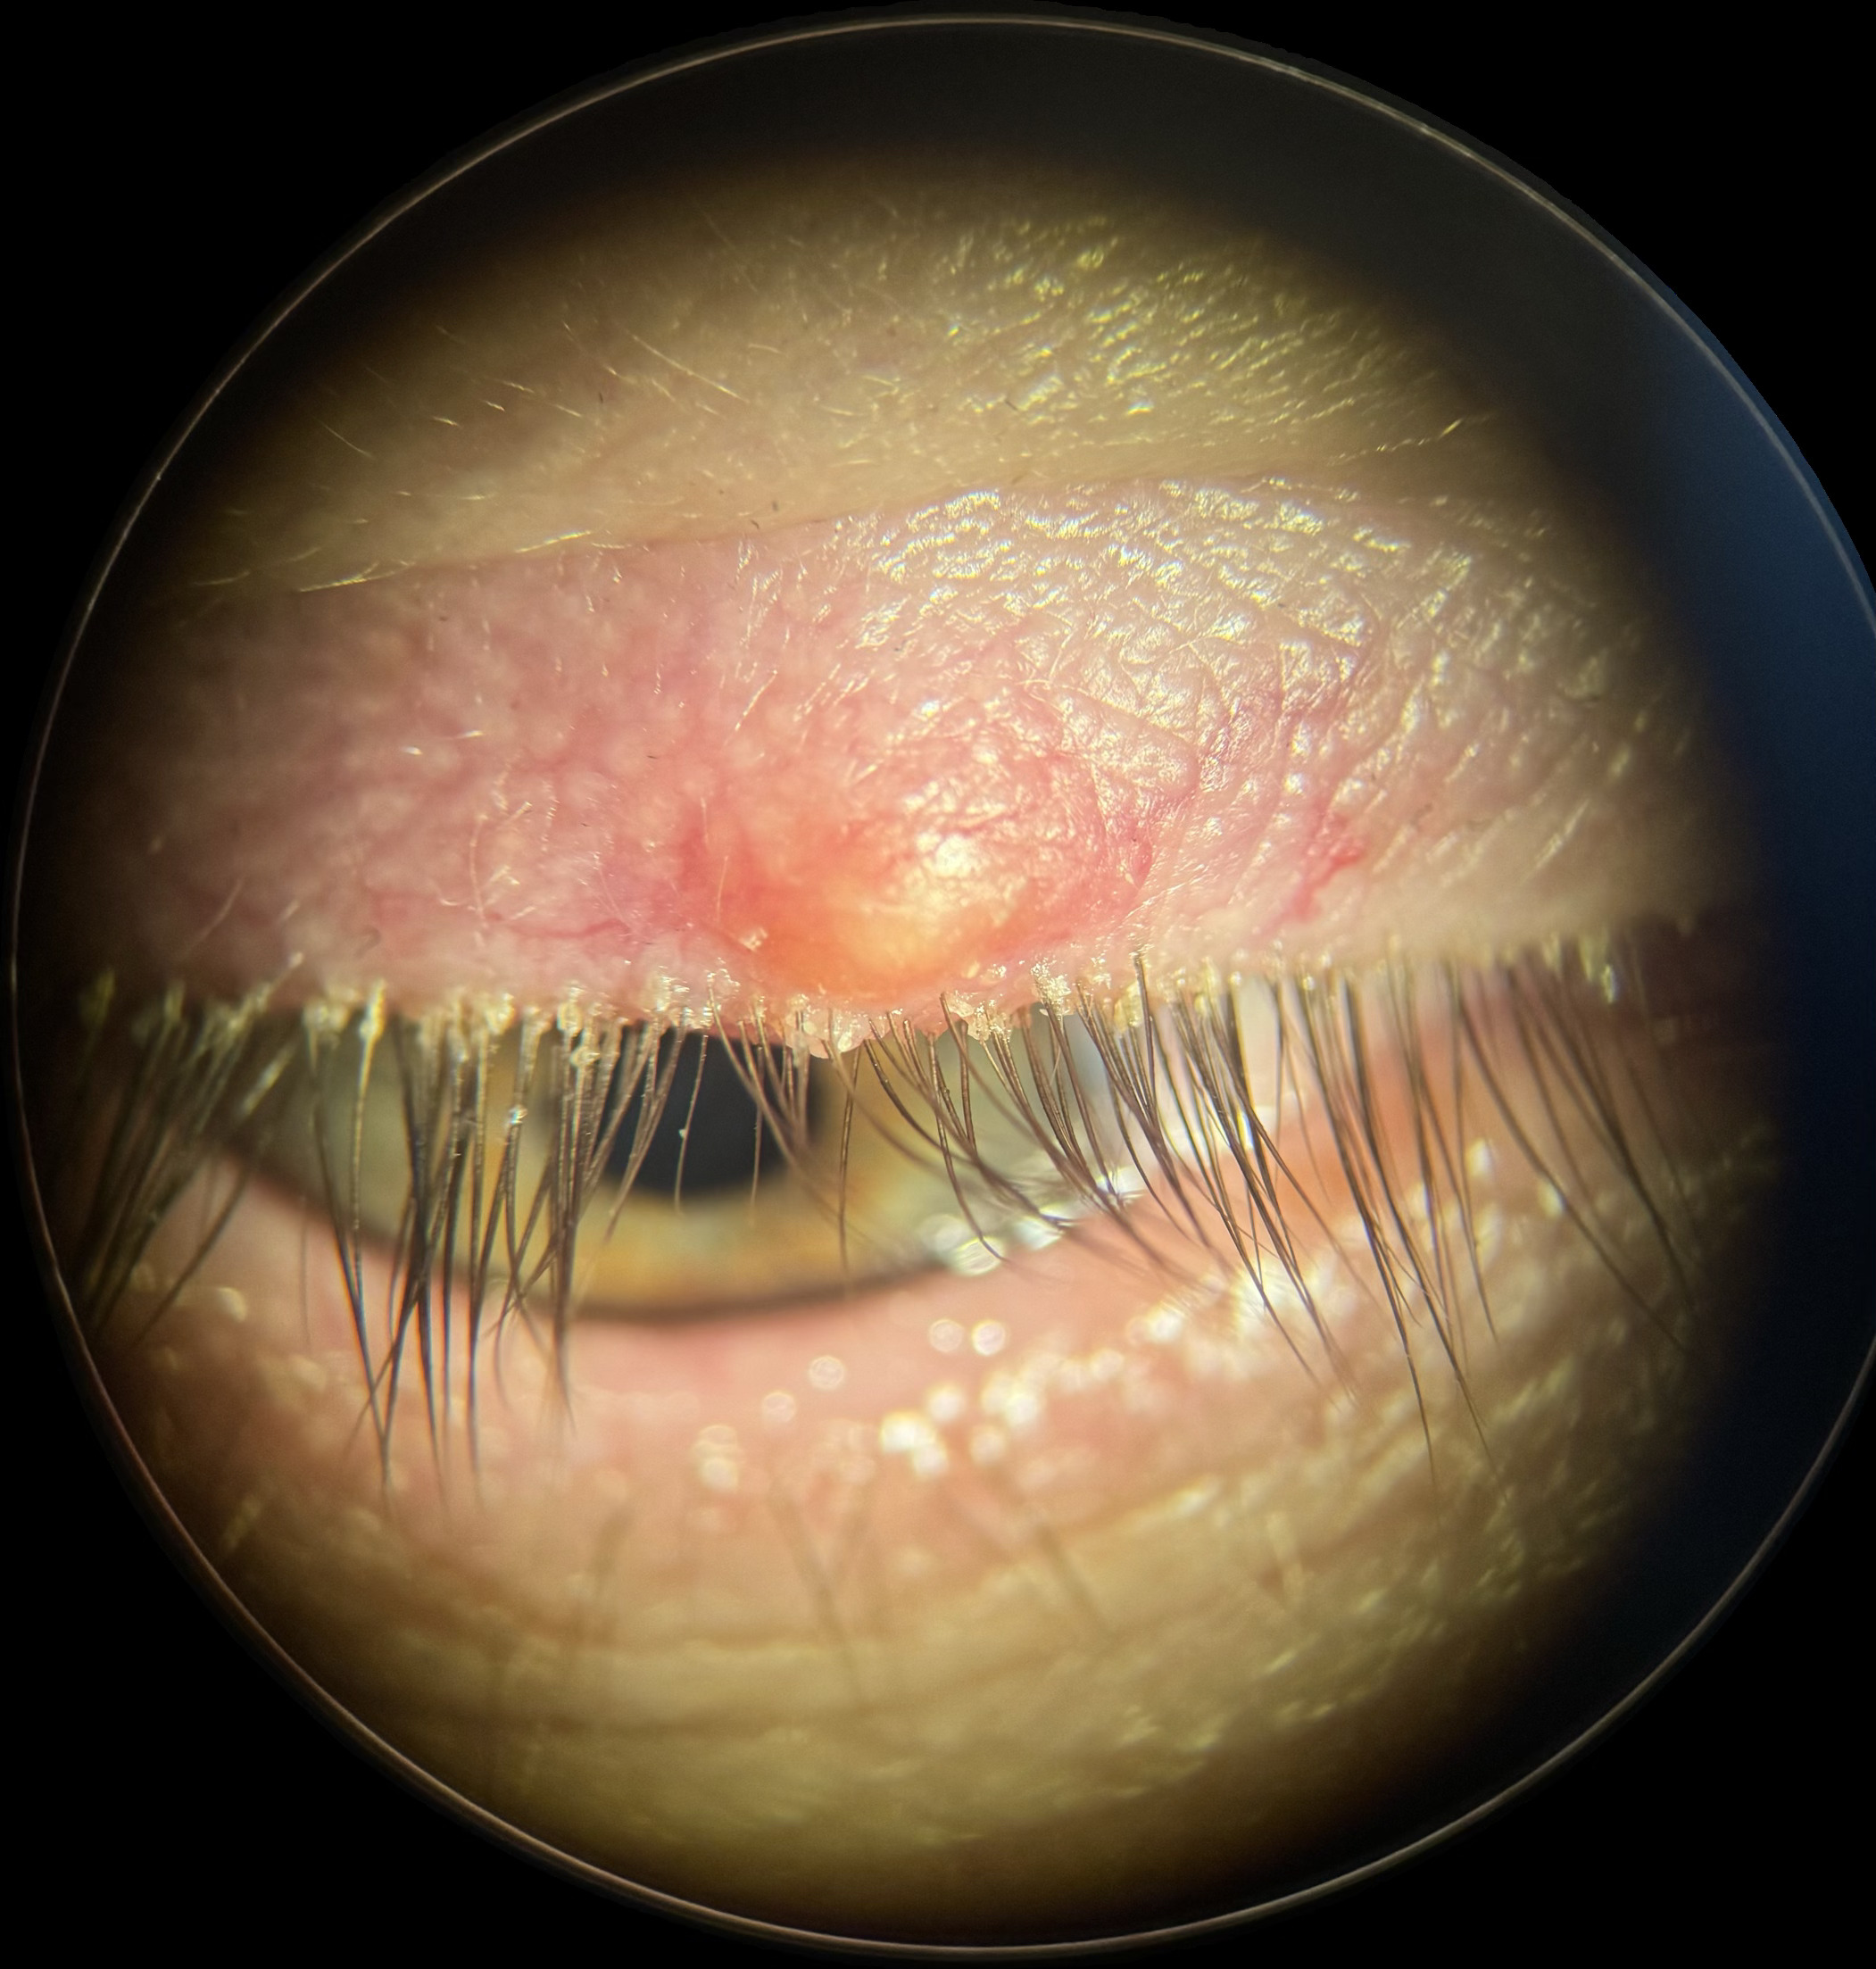

WHAT IS BLEPHARITIS

Blepharitis is an infection of the eyelash glands and eyelids. The infections are usually bacterial or from a mite (Demodex). Because this infection affects the tear glands, it causes a disruption of the important function of the tears and results in a Dry eye syndrome.

HOW IS BLEPHARITIS DIAGNOSED

Blepharitis infection is almost always associated with dry eye syndrome. This complex relationship requires meticulous diagnostic tests & management by Dr. Djan at the Advanced Dry Eye Clinic. The reasons for this are simple: No two people with blepharitis/dry eye syndrome have the same degree or cause of pathology. Tests are required to diagnose your specific degree of blepharitis so that a custom solution can be designed for you.

These diagnostic eye tests that Dr. Djan performs at the advanced Dry Eye Clinic are all non-invasive and include :

HOW IS BLEPHARITIS TREATED

A customised dry eye syndrome treatment is designed once your comprehensive assessment is complete. Depending on your classification, there a various options available to tackle DES: